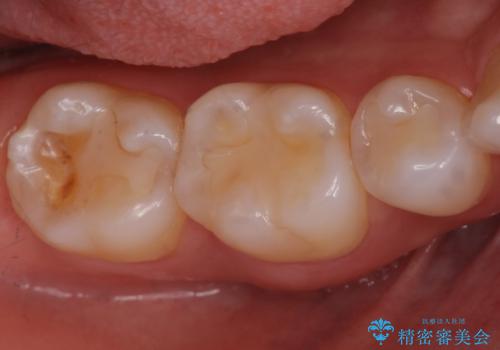

笑うと外からも見える位置であるため、白いセラミックでの治療となりました。

- 右上5 セラミックインレー 77000円×1本費用は治療当時の料金となります

局所的に深い虫歯が確認されましたが、神経は温存することができました。